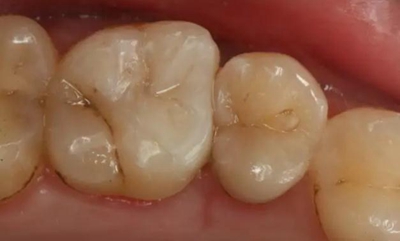

病例一 女性,20歲,大學(xué)生,要求補(bǔ)牙,檢查口內(nèi)可見A6大面積缺損,近中牙齦息肉,拍X片,根管充填物略差,但根周未見明顯陰影,口內(nèi)檢查無(wú)叩痛。建議患者冠延長(zhǎng)手術(shù)+高嵌體修復(fù)。

患牙遠(yuǎn)中邊緣嵴完整,強(qiáng)度沒(méi)有降低,故擬保留遠(yuǎn)中邊緣嵴,高嵌體修復(fù)。首先去除腐質(zhì)及原墊底材料,流體樹脂+3M Z350XT樹脂墊底。局麻下行冠延長(zhǎng)手術(shù)。在此需要提及個(gè)人的一個(gè)觀點(diǎn)。冠延長(zhǎng)手術(shù)原則上要求3-6個(gè)月以上才能永久修復(fù)。但是個(gè)人喜歡后牙肩臺(tái)建立在齦上,所以修復(fù)后的修復(fù)體邊緣位于牙齦上方1mm,對(duì)牙周的愈合影響較?。ㄈ绻麨辇l下邊緣則要慎重),故該患者術(shù)中按照齦上邊緣的設(shè)計(jì)進(jìn)行冠延長(zhǎng)手術(shù)。以下為術(shù)中: